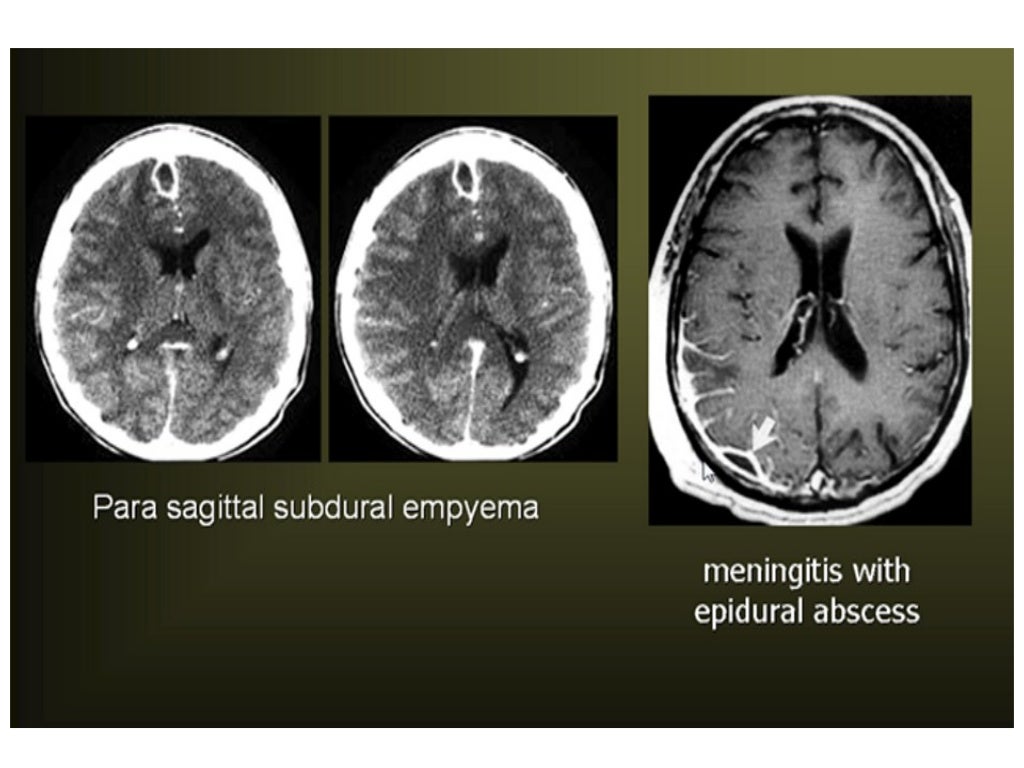

From health-fts.blogspot.com

HEALTH FROM TRUSTED SOURCES Brain CT MRI Signs Symptoms Brain Infection It can be life threatening and requires. A brain infection is a bacterial, viral, fungal, or parasitic infection of the tissue of the brain itself or the membranes surrounding. Early warning signs of infective encephalitis include: And when it's caused by the. Meningitis is an infection and swelling, called inflammation, of the fluid and membranes around the brain and spinal. Signs Symptoms Brain Infection.